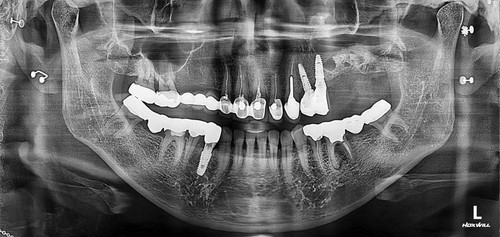

상악동누공폐쇄술이 성공하면 그 다음 단계로는 치조골 이식과 임플란트 식립을 해야 하는데 간혹가다 일반적인 상악동거상술에 비하면 누공이 있었던 부위는 상악동점막과 잇몸살이 유착되어서 힘든 경우가 많습니다. 물론 폐쇄술을 시행하면서 상악동에 뼈이식을 동시에 하는 것도 하나의 방법이 될수 있겠으나 성공했을 때 뿐만 아니라 누공폐쇄술이 실패했을 때를 가정한다면 통상적으로 동시 뼈이식을 시행하기에는 다소 위험성이 따르는 것이 사실입니다. 그래서 이 환자분은 안전하게 단계적으로 진행하기로 하였으며 누공폐쇄술이 성공한 후에 상악동 측방거상술을 시행하였고 이식한 뼈가 충분히 굳은 후에 임플란트를 식립하였습니다.

임플란트를 식립한 후에는 통상적으로는 3개월 후에 임플란트 보철물이 들어가는데 환자분의 사정으로 치과 내원을 못 하셔서 약 5개월 후에 오셨는데 왼쪽 아래 치아의 뿌리 부위의 충치가 발견되어서 아래 치아는 발치하면서 식립하는 즉시식립을 해 드렸습니다.

보통 하악에 임플란트 식립하면 2개월 이내에 치아가 들어가는데 마찬가지로 환자분 사정으로 못 오시다가 6개월이 지나서야 위,아래 임플란트 머리가 들어가고 마무리 할수 있었습니다.